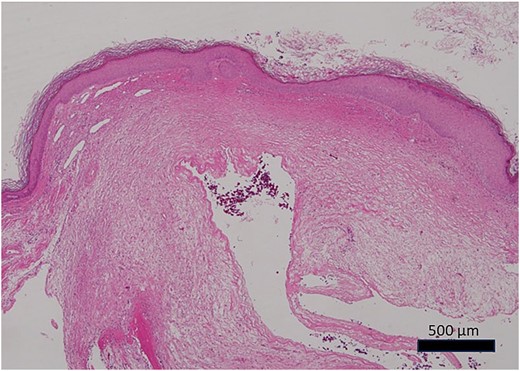

Histopathological findings showed an edematous subcutaneous lesion in the mucosa of the external auditory canal with a cyst. The cyst was not covered by epithelium and had a ganglion-like appearance (Fig. 6). Osteocytes on the inner surface of the mandibular head showed no tumor-like changes. Still, there were substantial changes in the surface cartilage. This was consistent with osteoarthritis.

Photomicrograph of the histopathological specimen (HE staining). The cyst had no epithelial covering, mixoid-like changes, and ganglion-like findings.